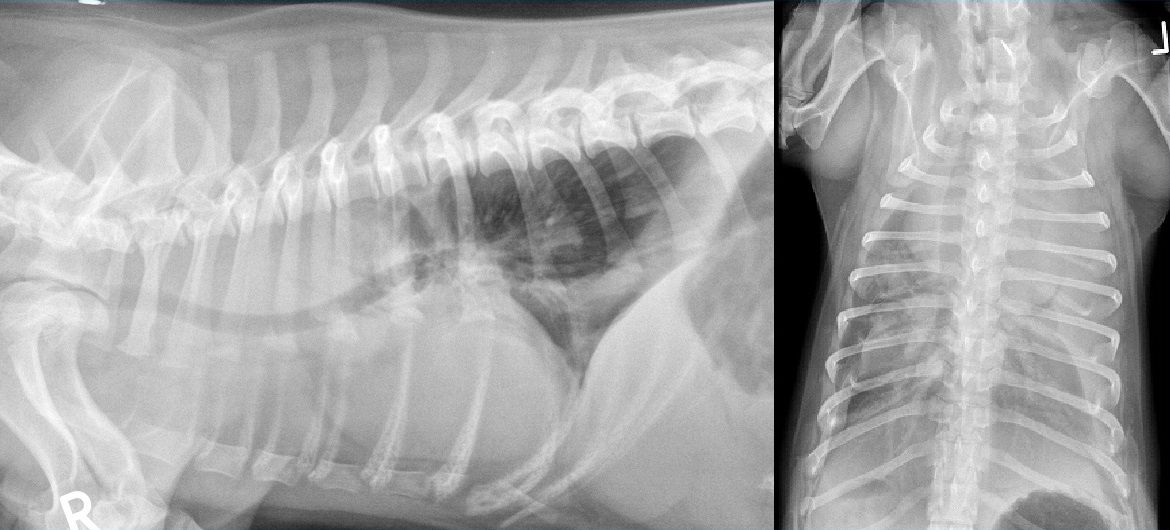

From www.vetpixel.com

Cas Un cas de jabot oesophagien secondaire a une persistance du Jabot Oesophagien Chat L’hypomotricité oesophagienne, une prédisposition génétique du siamois, est une des causes de mégaoesophage. Une prédisposition raciale est constatée chez le. Oesophagite chez le chat et le chien : Dans ce cas, il est fréquent que le chat ait bon. Le jabot oesophagien est une dilatation localisée de l'oesophage qui résulte d'une malformation vasculaire congénitale (persistance du 4 ème. Chez le. Jabot Oesophagien Chat.